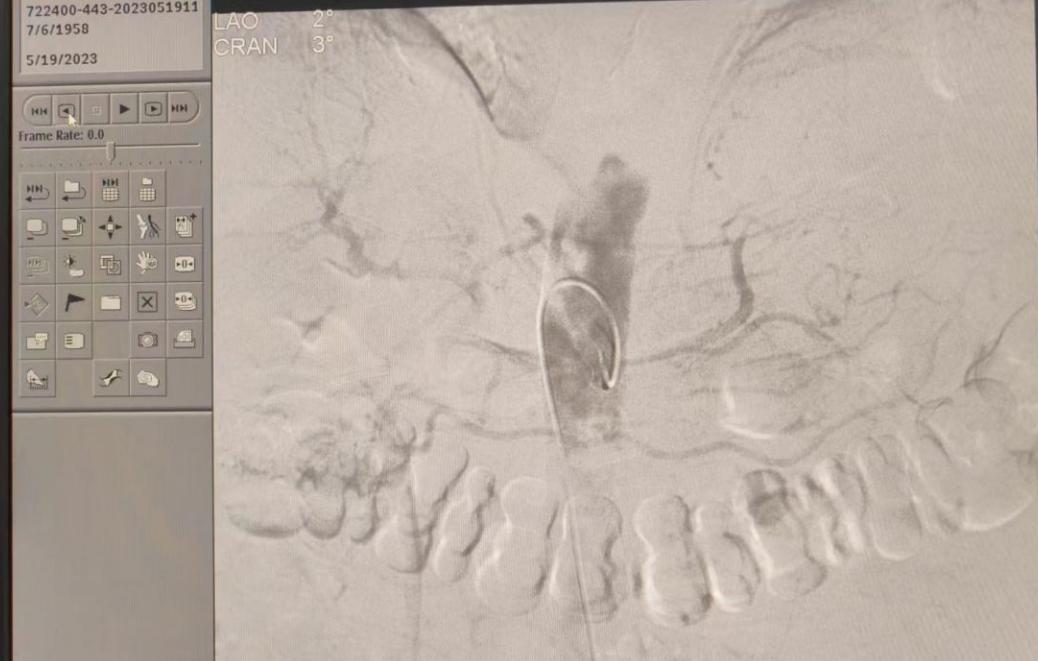

造影中(如下)

肝动脉造影结果显示:腹腔干动脉稍扭曲,肝动脉稍增粗,右肝上缘S8段可见一球形肿瘤染色区,右肝下缘S6段肿块状淡染色区,未见明显血管畸形及动静脉瘘。初步判断肝S8肿瘤染色区为肝癌病灶,肝S6肿块染色区为肝脏再生结节,肝癌的癌前病变可能。